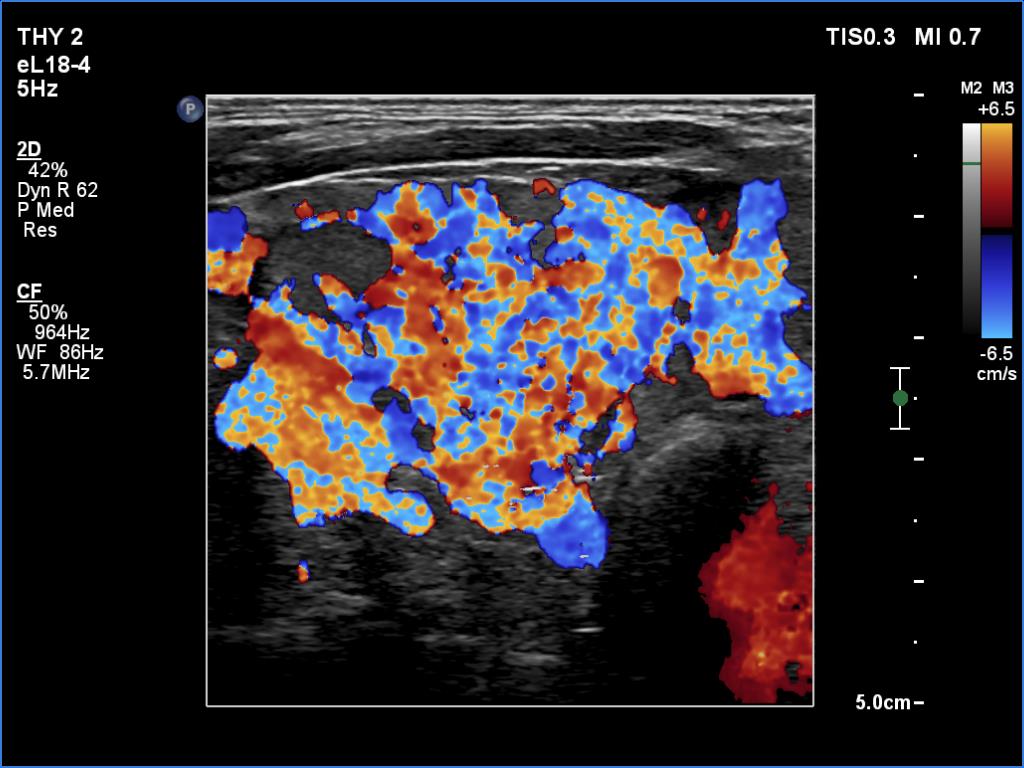

Second examination 6 years later (second row of images):

Clinical data: The patient was referred for a follow-up.

Palpation: unchanged.

Laboratory tests: TSH 3.52 mIU/L.

Ultrasonography. The pattern was the same as in the previous study except for the lesion in the isthmus which has been increased in size.

Suggestion: TSH in a year, ultrasound in 3 years.

Comment. This is the typical presentation of the micronodular form of Hashimoto's thyroiditis.